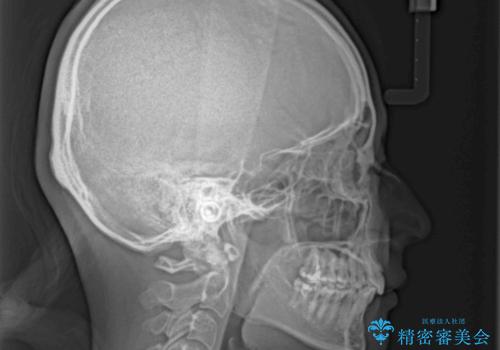

飛び出した前歯を引っ込めたい 目立たないワイヤーでの抜歯矯正

- 口元の閉じにくさと、前歯のでこぼこの歯並びを気にして来院された患者様です。

口元を積極的に引っ込めるために、上下左右の小臼歯計4本を抜歯することとしました。

咬み合わせが深く、咬合力強いため、補助装置を使用しながら積極的に口元を下げることとしました。

矯正治療終了近くに九州へ引っ越すことになってしまい、なかなか来院することができなくなったため、引っ越してから1年以上の期間が必要となってしまいました。